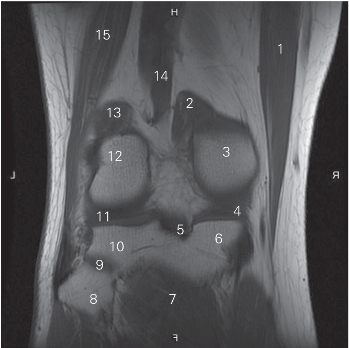

图5-30 经近侧胫腓关节的冠状断层MR T1加权图像

1 缝匠肌 sartorius 2 腓肠肌内侧头 medial head of gastrocnemius

3 股骨内侧髁 medial condyle of femur

4 内侧半月板 medial meniscus

5 后交叉韧带 posterior cruciate ligament

6 胫骨内侧平台 medial tibial plateau

7 腘肌 popliteus 8 腓骨头 head of fibula

9 胫腓上关节 superier tibiofibular joint

10 胫骨外侧平台 lateral tibial plateau

11 外侧半月板 lateral meniscus

12 股骨外侧髁 lateral condyle of femur

13 腓肠肌外侧头 lateral head of gastrocnemius

14 腘动脉 popliteal artery 15 股二头肌 biceps femoris